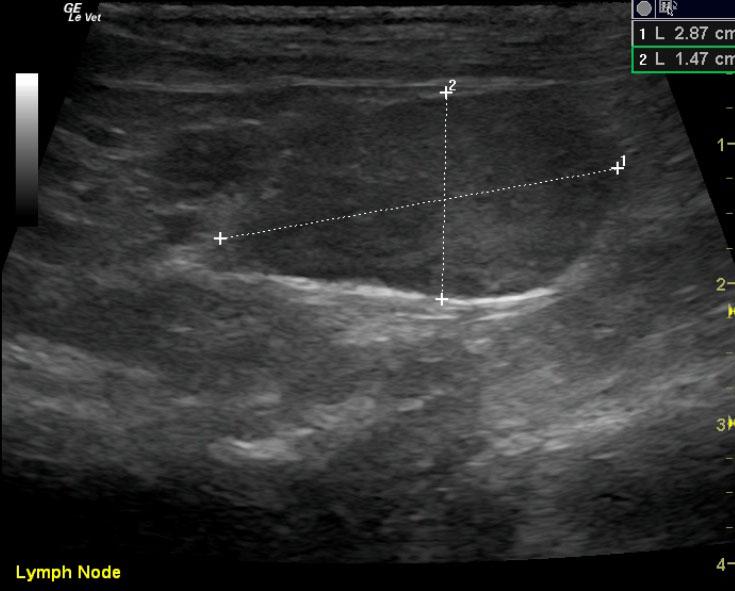

Pyloric outflow was mildly prominent in this patient with hypertrophy of the muscularis and mildly increased echogenicity of the submucosa layer. The remainder of the intestinal tract revealed thickened submucosal layers. Jejunal lymph nodes were enlarged at 2.87 x 1.47 cm with uniform contour, and the egg shape formation would be more suggestive of reactive lymphadenitis.

The patient was still not 100% after 1 month of antibiotics, inflammatory leukogram 2% bands. Recheck ultrasound revealed the caudal abdominal lymph nodes were persistently enlarged, yet less reactive and measured 2.84 x 1.07 cm. They were uniformly, prominently echogenic. Iliac lymph nodes were also unremarkable at this time compared to the prior to sonogram and measured 1.22 x 0.47 cm on the right. Structurally this patient appears improved with minor residual mesenteric lymphadenopathy. Continuation of the current protocol would be recommended unless the patient demonstrates persistent clinical signs.